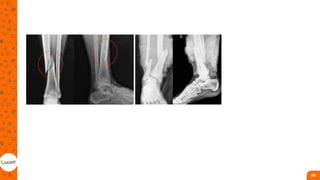

Fratura de diáfise da tíbia

• Ocorrem na maior parte dos casos, devido a

traumas de alta energia, como acidentes de

trânsito, quedas de altura e esportes de

contato;

• Como a tíbia é um osso com pouca

cobertura muscular, a maioria das suas

fraturas – fechadas e expostas – está

associada à lesão da pele e do tecido

subcutâneo.

• Um ponto importante a ser considerado é a

síndrome compartimental, que ocorre com

maior frequência e necessita de cirurgia

imediata para a liberação da fáscia

Fratura de tornozelo

• Fraturas deslocadas e/ou instáveis

geralmente requerem cirurgia para restaurar

e manter a congruência ósseo-ligamentar,

sendo utilizadas técnicas de redução aberta

e fixação interna;

• Fraturas graves de calcâneo podem causar

deslocamento de todo o osso e suas

superfícies articulares, sendo a articulação

subtalar a mais afetada;

• Nesses casos, o tratamento conservador

não é promissor. Tendo-se em vista que

pode ficar com a junção incongruente,

calcâneo deformado, perder o alinhamento

tornozelo-calcanhar, assim como ter dor

local e osteoartrite na articulação subtalar, a

função do paciente é seriamente

comprometida